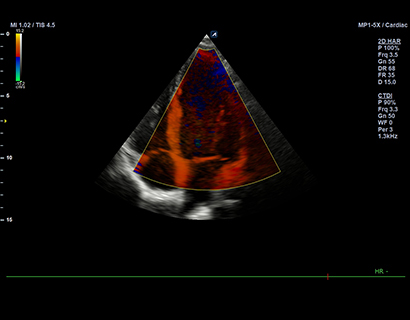

MP1-5X(NEW)

X+ Crystal Signature™ phased array (1~5MHz)

Application:

Cardiac, TCD, EM, Abdomen, Pediatric